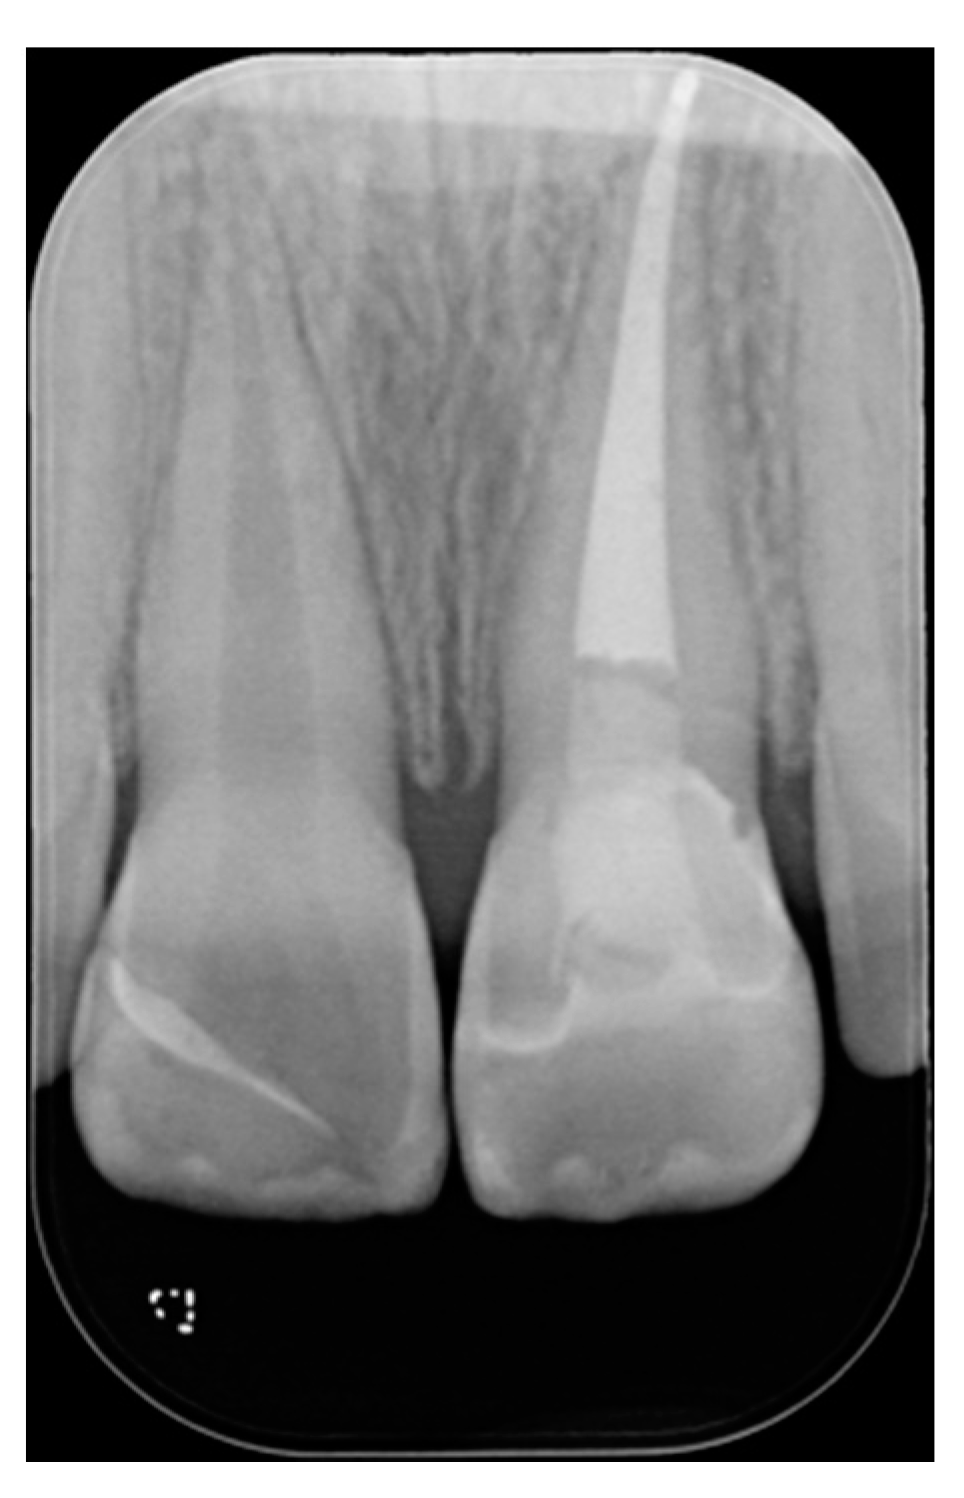

Figure 17.

One year post-operative x-ray. Reprinted from Restauri diretti nei settori anteriori, G. Paolone, S. Scolavino, © 2021, with permission from Quintessence Publishing Italy.

Figure 18.

Five years post-operative.

Figure 19.

Five years post-operative x-ray.